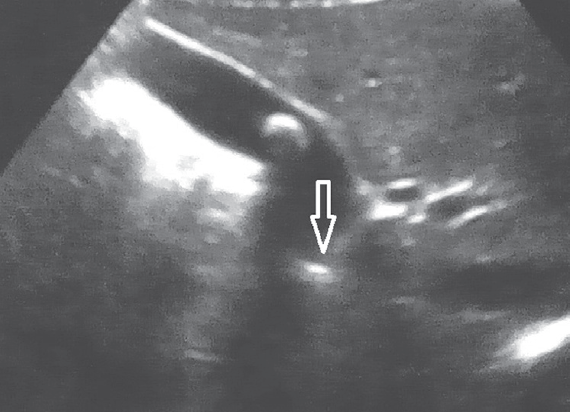

Проведенное в дооперационном периоде УЗИ гепатобилиарной системы выявило у всех пациентов с ЖКБ различные варианты деформации в области пузырного протока (рис. 4).

Рис. 4. Ультразвуковая картина деформированного пузырного протока

Fig. 4. Ultrasonic pattern of deformed cystic duct